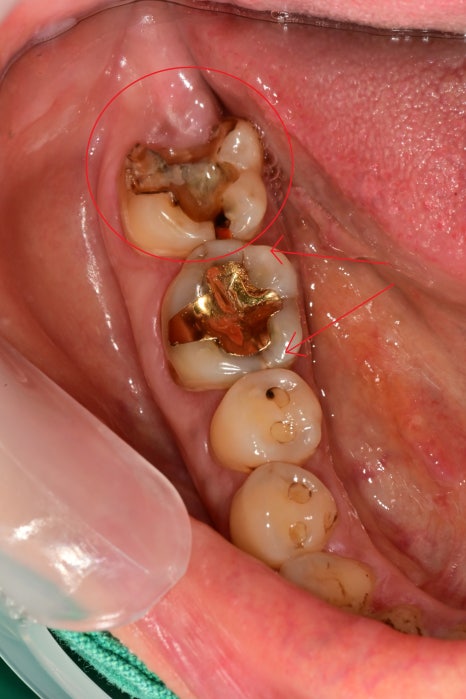

오늘 소개해 드릴 케이스는

치아에 다발성 크랙이 발견되고

치아파절까지 관찰된 환자분입니다.

구강 내에서는 아래쪽 뿐 아니라

대합 되는 부위에서도 다발성의 크랙이 관찰되었습니다.

치아의 파절과

좌우로 진행된 금간 부위 하방으로

2차 우식까지 진행되었습니다.